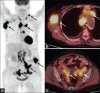

Generalized lymphadenopathy is a common and often vexing clinical problem caused by various inflammatory, infective and malignant diseases. We aimed to review briefly and highlight the potential role of (18)F-2-fluoro-2-deoxy-glucose ((18)F-FDG) positron emission tomography/computed tomography (PET/CT) in such patients. (18)F-FDG PET/CT can play an important role in the management of generalized lymphadenopathy. It can help in making an etiological diagnosis; can detect extranodal sites of involvement and employed for monitoring response to therapy.

- Karunanithi S, Singh H, Sharma P, Naswa N, Kumar R. 18F-FDG PET/CT imaging features of Rosai Dorfman disease: A rare cause of massive generalized lymphadenopathy. Clin Nucl Med. 2014;39:268–9. - PubMed